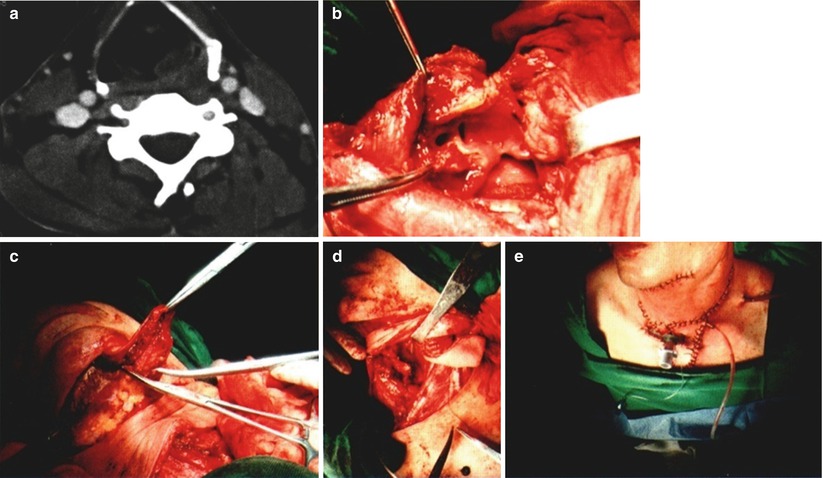

Fig. 14.1

Case I. (a). Design of platysma myocutaneous flap. (b) The primary focus of the hypopharyngeal cancer was resected. (c)The hypopharyngeal defect after resection of the primary focus. (d) The platysma myocutaneous flap was used to repair the hypopharyngeal defect. (e) The situation when the surgery was completed